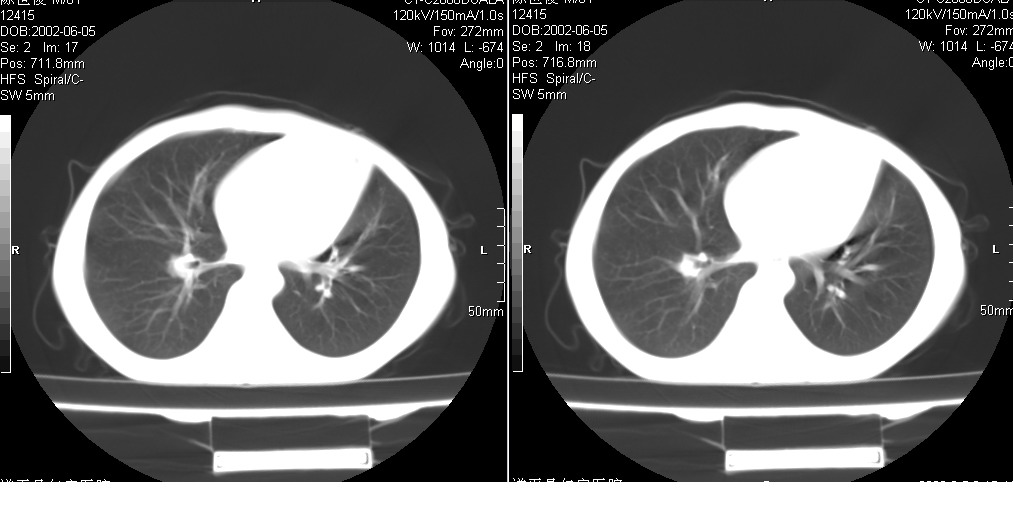

以下是引用xxhwh在2008-6-10 18:40:00的发言:[br]男,6岁,无规则发热一月余,体温在37.8——39度之间。一月前拍胸片示左上肺密度增高影,进行抗炎治疗8天,复查胸片未明显吸收。又改变抗菌素继续治疗半月,照胸片示病灶吸收不明显,行ct检查[br]征象:左上肺前段呈密实影,内可见支气管气像,远侧见絮状模糊影,中上纵隔左移。[br]意见:左上肺前段膨胀不全及感染,考虑为支气管异物或支气管内膜结核所致,[br]建议追问有无异物吸入史,行痰检及ppd检查